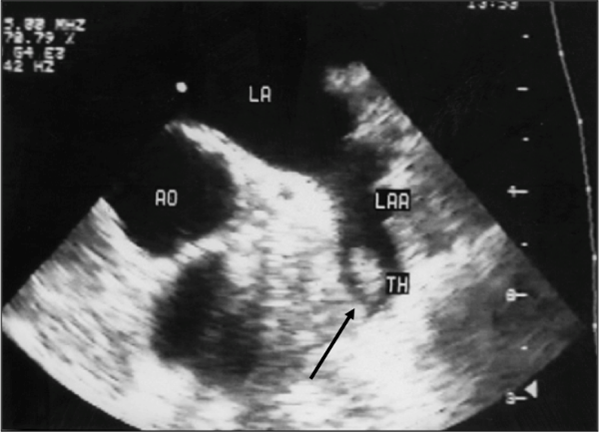

Certaines cardiopathies dites emboligènes favorisent la formation d’un thrombus dans le cœur (Fig. 5), lequel peut migrer dans la circulation cérébrale et occlure une artère cérébrale, provoquant un infarctus cérébral. De nombreuses cardiopathies peuvent être en cause. Les plus fréquentes sont la fibrillation atriale, les cardiopathies ischémiques et les maladies valvulaires cardiaques.

Fig. 5 : Échographie cardiaque montrant un thrombus (TH) dansl’oreillette gauche chez un patient ayant une fibrillation atriale (trouble du rythme cardiaque favorisant la formation d’un thrombus)